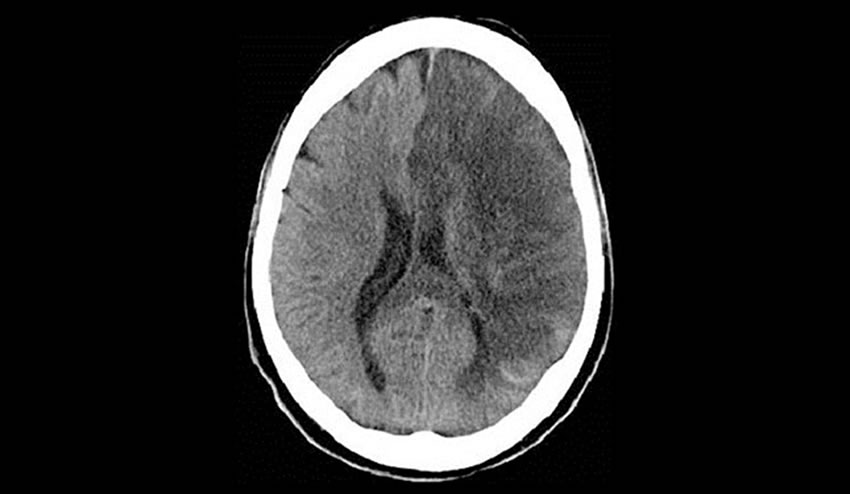

La parte oscura que se observa en el cerebro es a la que le falta irrigación. Cuando la embolia obstruye el flujo del lado derecho del cerebro, la parálisis será en la mitad del lado izquierdo del cuerpo y visceversa.

La parte oscura que se observa en el cerebro es a la que le falta irrigación. Cuando la embolia obstruye el flujo del lado derecho del cerebro, la parálisis será en la mitad del lado izquierdo del cuerpo y visceversa.